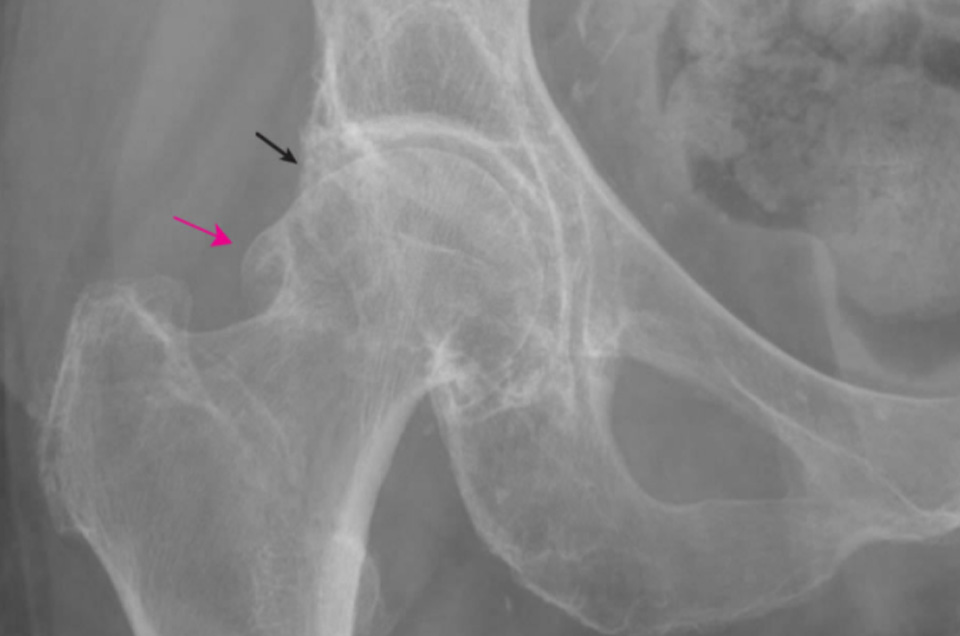

Osteoarthritis (OA)

고관절의 관절염은 무릎과는 달리 초기 중기까지도 일단 보존적 치료를 시행한다. 다만, 심한 경우는 유일한 대안이 인공관절 수술 뿐이다.

엑스레이 사진에서 고관절의 퇴행성 관절염 소견이 확인된다.

- 환자 동의하에 게시된 이미지입니다.